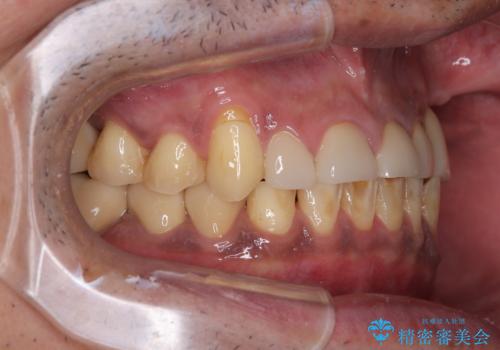

- すり減った前歯や奥歯の銀歯を気にして来院された患者様です。

骨格的な反対咬合により上顎前歯の先端が顕著にすり減っている状態でした。

奥歯の欠損が散見されており、銀歯の装着されている歯も多いため、ワイヤー矯正にて歯列を調整し、その後オールセラミッククラウンにて補綴治療を行うこととしました。

反対咬合改善には奥歯の咬み合わせをしっかりと改善させることが必要となりますが、奥歯に欠損が多いため、矯正治療が難航することが予想されます。